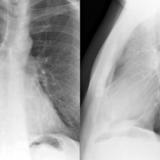

Case 2  Lung cancer and

Peric calcification

Case 2